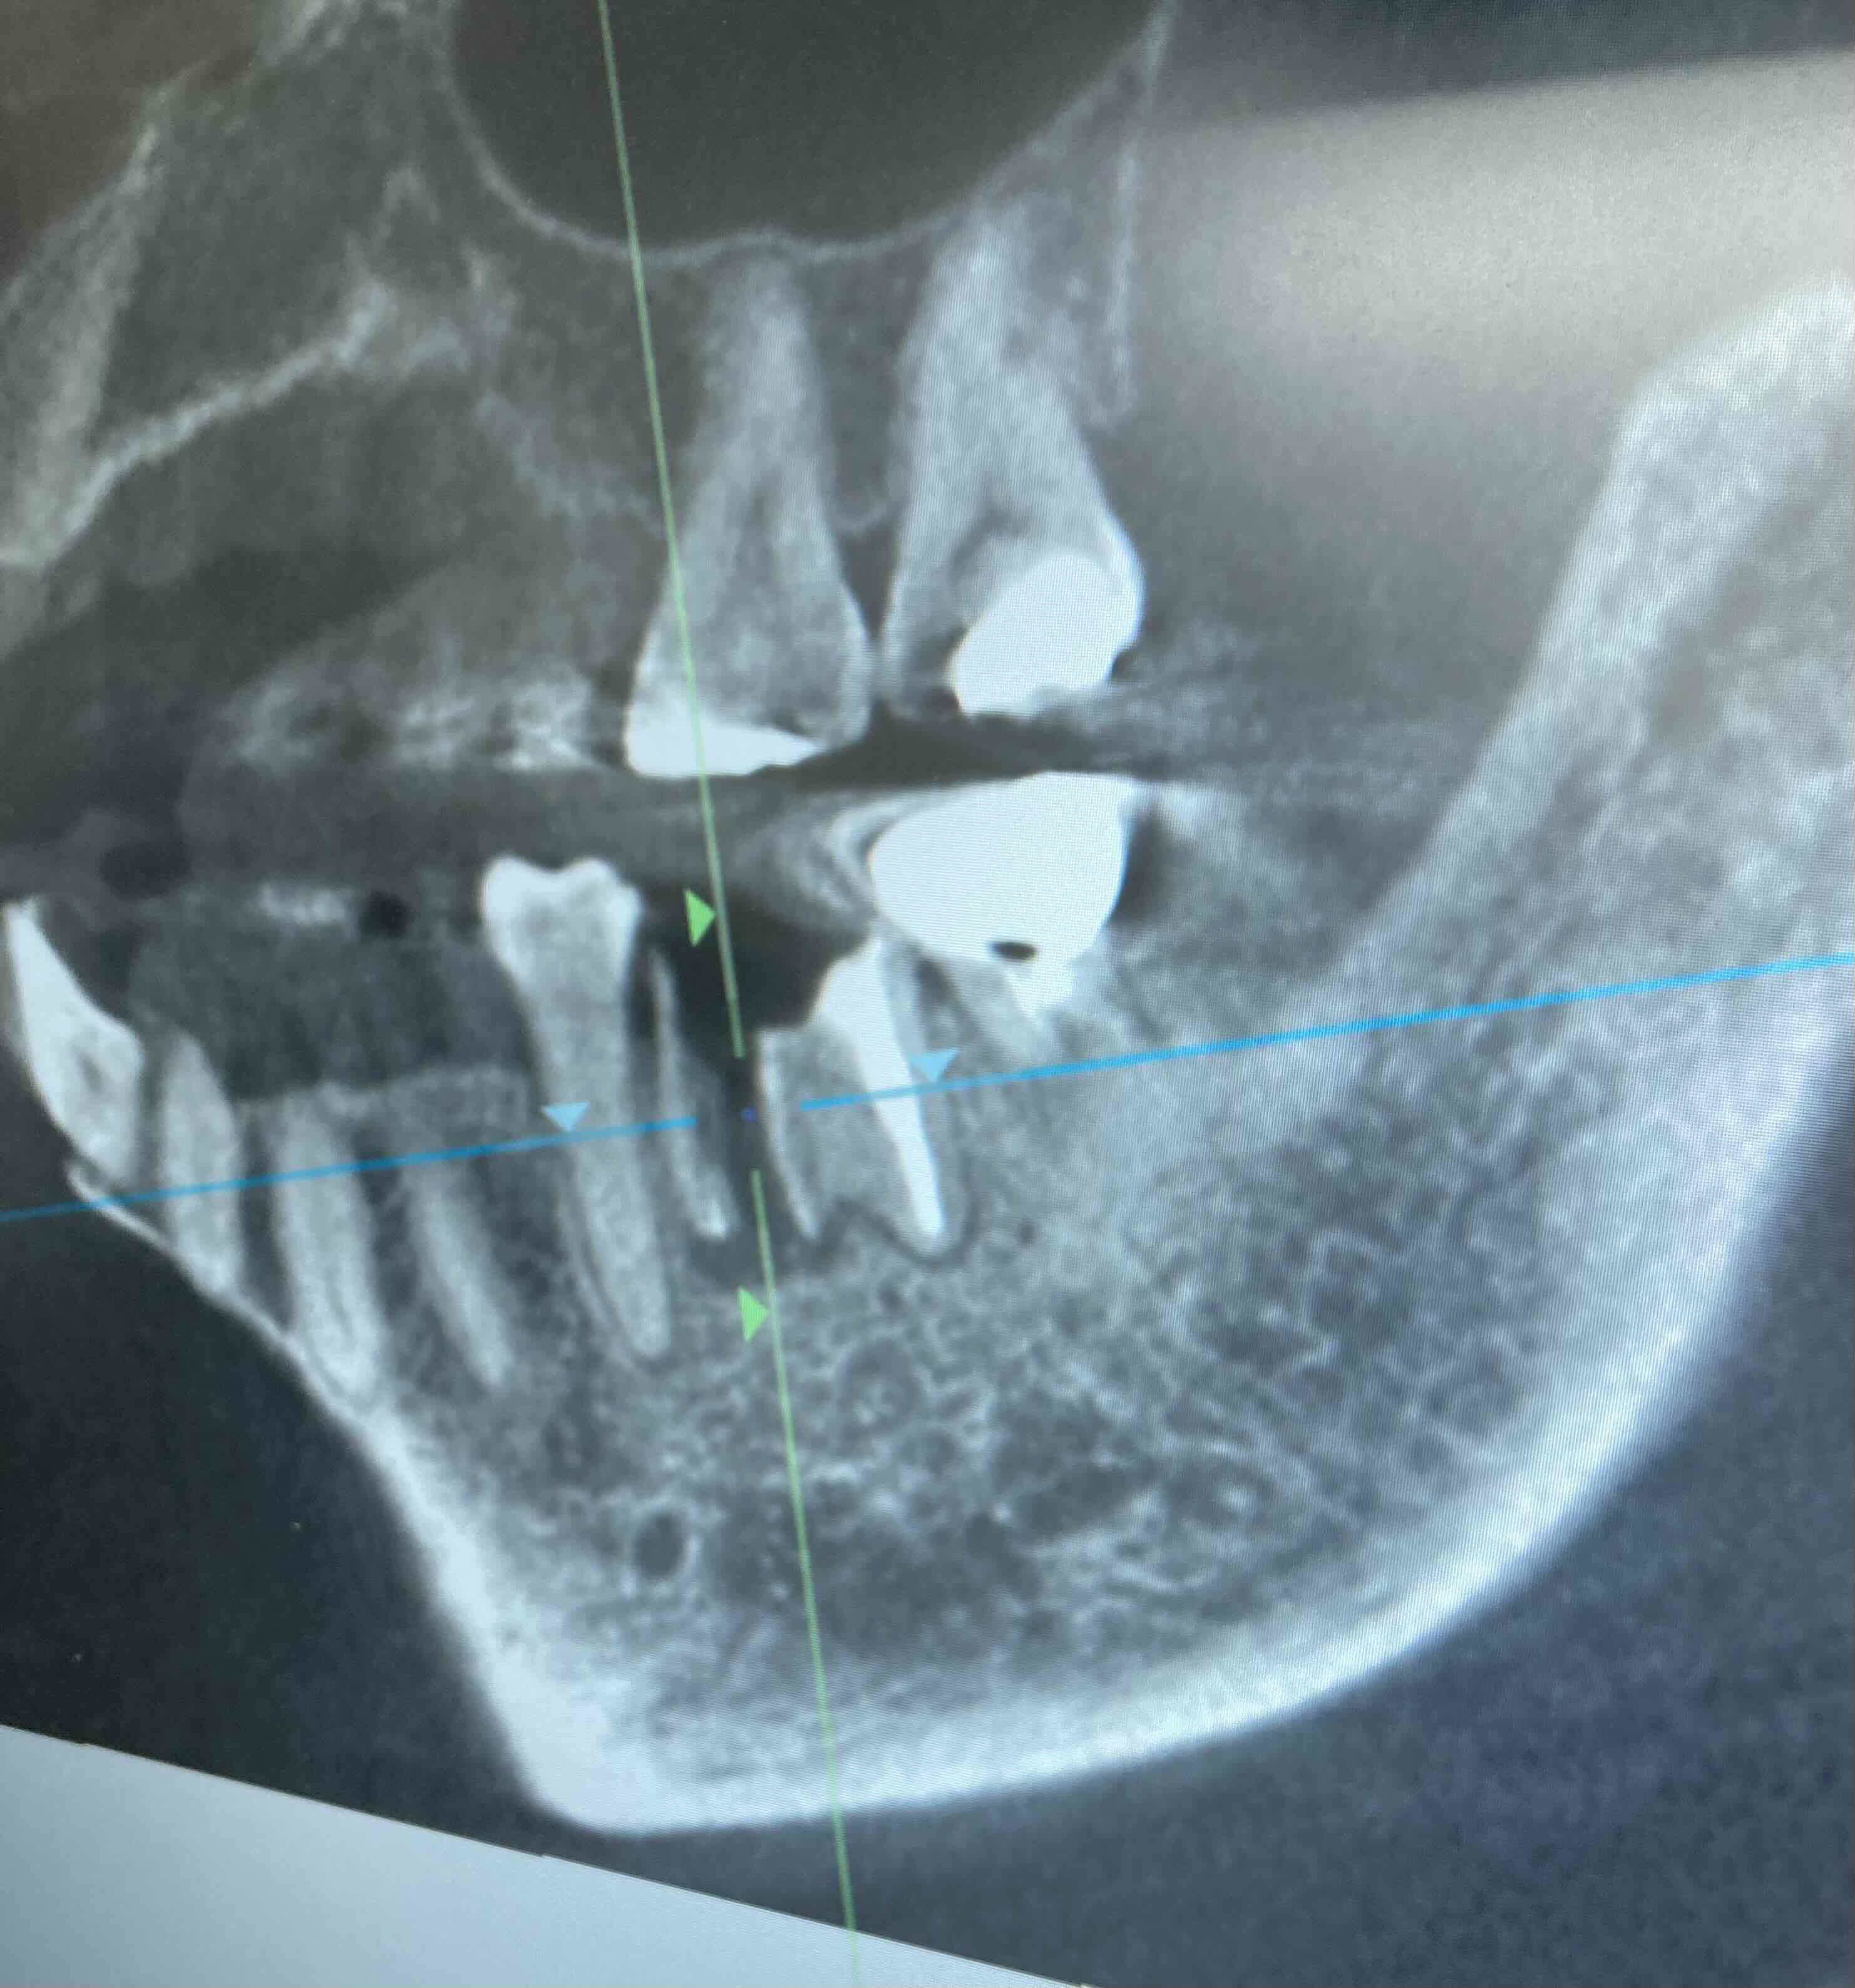

画像添付いたします

画像1CT.JPG 画像2レントゲン.JPG

近親根は真っ二つに割れていて炎症がかなりあるように見えていますが、5年間この根に何かを被せて使用されて来られたのでしょうか?現状の想像が難しいため回答が付き難かったのではないかと想像しました。

せっかくCT撮影もしていただいているようなのに、側方のからの画像しかアップされていないようですが、そもそも、歯根の垂直破折が確認された場合には、骨の温存を鑑み、速やかに抜歯するのが基本なのに、5年も放置してしまったとなると、「 ほんのわずかに骨吸収がはじまりつつある 」 どころか、少なくとも抜歯した時点では、頬側の骨がごっそりなくなっていることが、容易に想像されます。